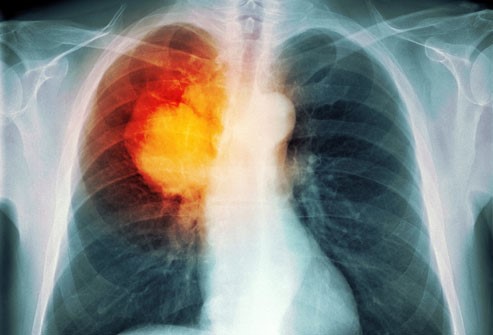

Профилактика злокачественных новообразований у населения